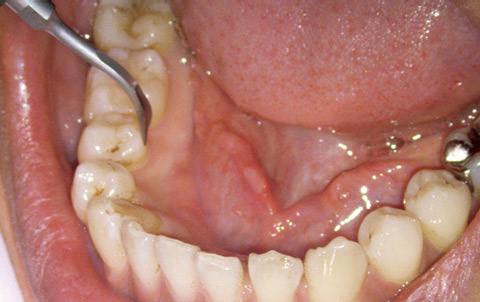

図2 超音波スケーラーを用いて歯石を除去。

図3 同、下顎右側頰側部分。